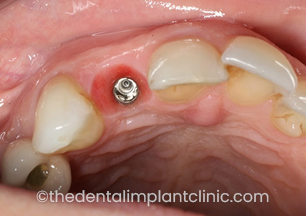

Implant placed at the UR2 site